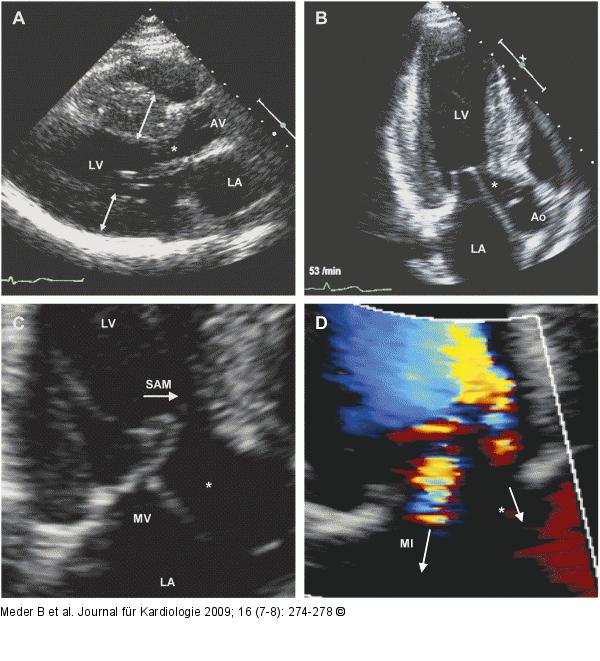

Abbildung 1: HOCM Echokardiographie eines Patienten mit HOCM. (A) Parasternale lange Achse: Das linksventrikuläre Myokard ist septal betont, konzentrisch massiv hypertrophiert (Septumdicke ca. 26 mm). (B) Apikaler Dreikammerblick: Partielle Obstruktion des LVOT mit einem dopplersonographisch gemessenen Ruhegradienten von ca. 130 mmHg. (C) Das SAM-Phänomen des anterioren Mitralsegels führte bei diesem Patienten zu einer mittelgradigen Mitralklappeninsuffizienz (MI) (D). LA = linkes Atrium; LV = linker Ventrikel; * = LVOT, AV = Aortenklappe; MV = Mitralklappe; SAM = "systolic anterior motion". |